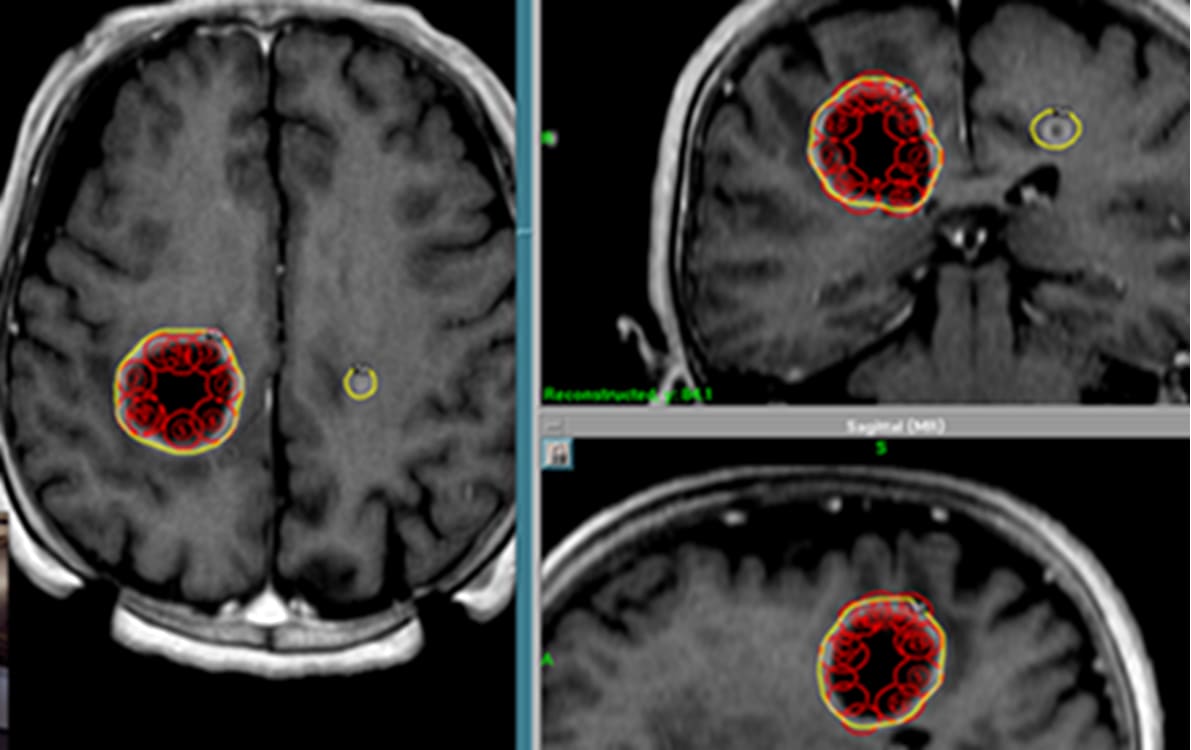

巨大のう胞性転移性脳腫瘍(乳がん)

ガンマナイフ症例に対する治療計画(左)と3か月後経緯(右)